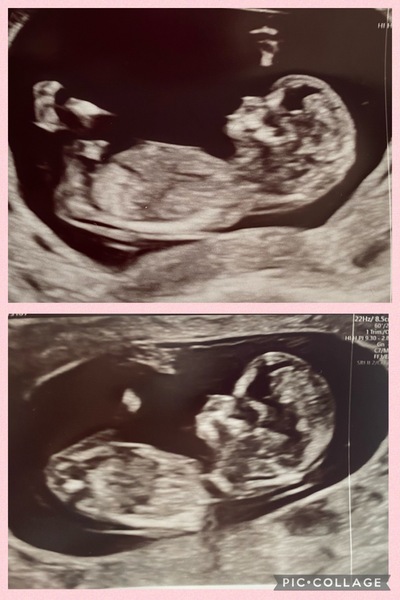

TheLemonBear · 18/05/2024 17:14

Hi, had my scan yesterday.. 12 weeks exactly.. can anyone see a nub? Or do the skull theory?

thanks

Skull theory